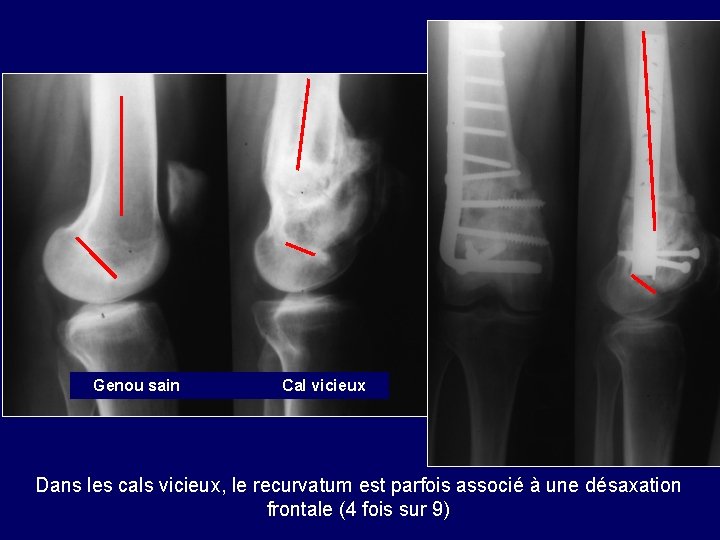

Genou sain Cal vicieux Dans les cals vicieux, le recurvatum est parfois associé à une désaxation frontale (4 fois sur 9)